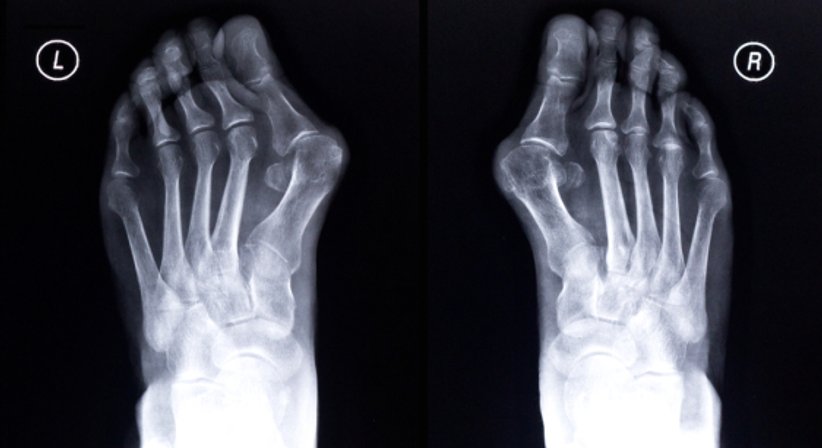

Hallux valgus

Der Hallux valgus (auch als Ballenzeh, Überbein oder Frostbeule bekannt) ist durch eine Fehlstellung der Großzehe gekennzeichnet. Der Schiefstand der großen Zehe ist nach seitlich außen gerichtet. Ein Hallux valgus wird vor allem durch das Tragen von zu engen oder zu hohen Schuhen verursacht. Somit sind primär Frauen vom Ballenzeh betroffen. Durch die Zehenverformung können Druckstellen entstehen. Außerdem kann die Fehlstellung Entzündungen, Schwellungen und starke Schmerzen hervorrufen. Da der Verlauf des Hallux valgus fortschreitend ist, empfehle ich den Betroffen eine operative Stellungskorrektur.